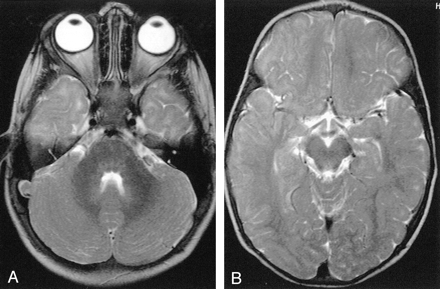

A and B, Axial T2-weighted MR images show grade 0 myelination in the temporal lobe. Subcortical T2 hyperintensity is recognizable in both temporopolar (A) and temporolateral (B) areas.